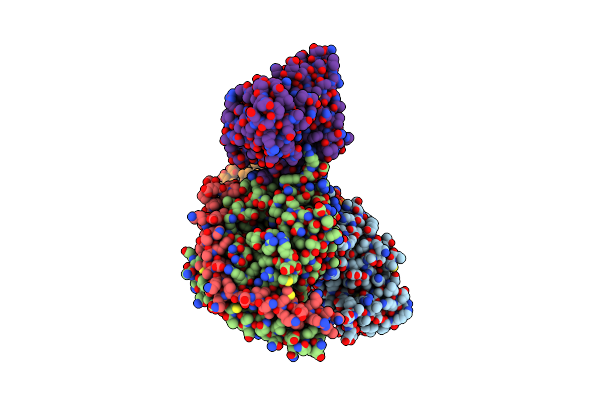

Cryo-Em Structure Of Ligand Histamine-Bound Histamine H4 Receptor Gi Complex

Organism: Homo sapiens

Method: ELECTRON MICROSCOPY Release Date: 2023-12-20 Classification: MEMBRANE PROTEIN Ligands: ITF |